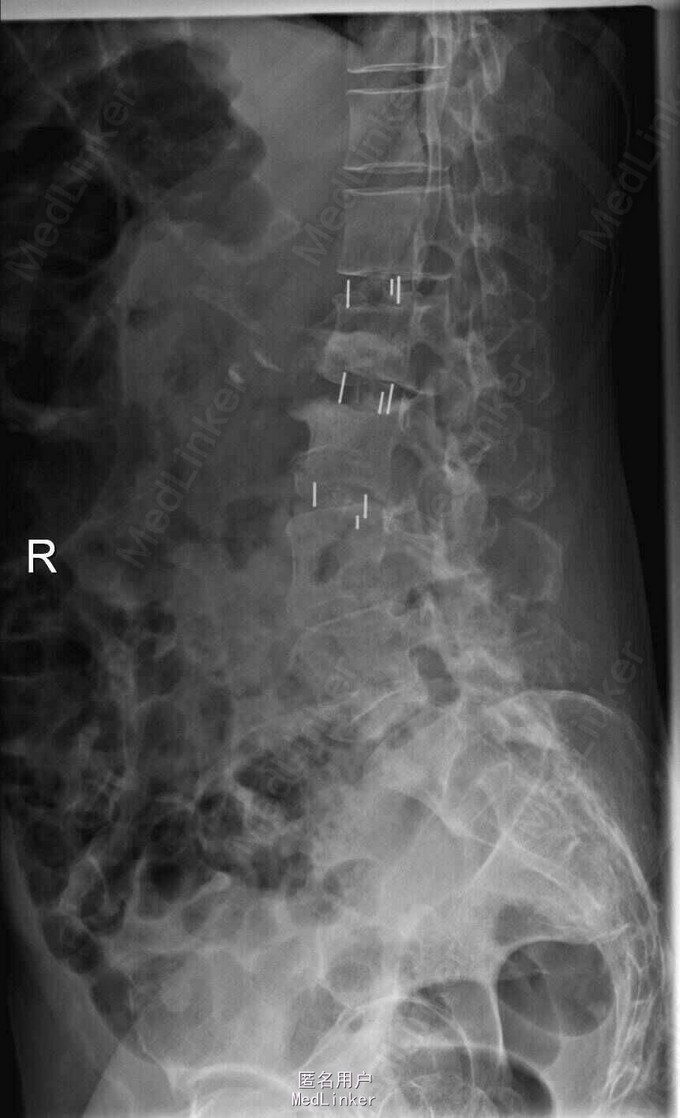

查体:脊柱侧弯,上肢无麻木,疼痛感觉异常,腰部右侧疼痛,右下肢及右臀部疼痛,麻木感。双侧肌力及肌张力可,膝腱反射(+),踝反射(+),病理征(—),直腿抬高试验。右侧40度,左侧55度。 辅助检查:腰椎x线片:腰椎侧弯,腰椎退行性改变,L5椎体略行前滑脱 脊柱全长:胸腰段呈S形,L5椎体向前滑脱,L3椎体略变扁,颈胸腰椎退行性改变 MRI:脊柱侧弯,L2-3,L3-L4,L4-L5,L5-S1椎间盘突出,相应节段椎管狭窄

诊断:腰椎侧弯,腰椎椎管狭窄 治疗:手术矫形:早期侧路减压融合,后期再行后路固定。

随访:病人初期手术时间段,术后恢复较快,病人神经压迫症状解除,腰部侧弯获得一定程度的矫正,术后起床用支局支撑后,可以下床活动,后期手术行后路经皮内固定。